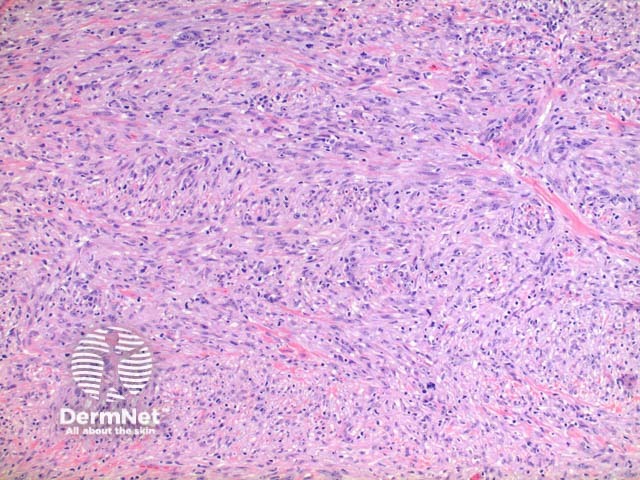

Scanning power view of histology of leiomyosarcoma shows a poorly circumscribed tumour nodule which may be dermal based in the less common dermal leiomyosarcoma (Figure 1) or deeply infiltrating in the subcutaneous form. The tumour is comprised of a spindle cell proliferation forming rough bundles and fascicles (Figures 2 and 3). High power demonstrates spindle cells with cigar shaped nuclei with prominent cytologic atypia and mitotic figures (Figures 4 and 5).

Figure 3